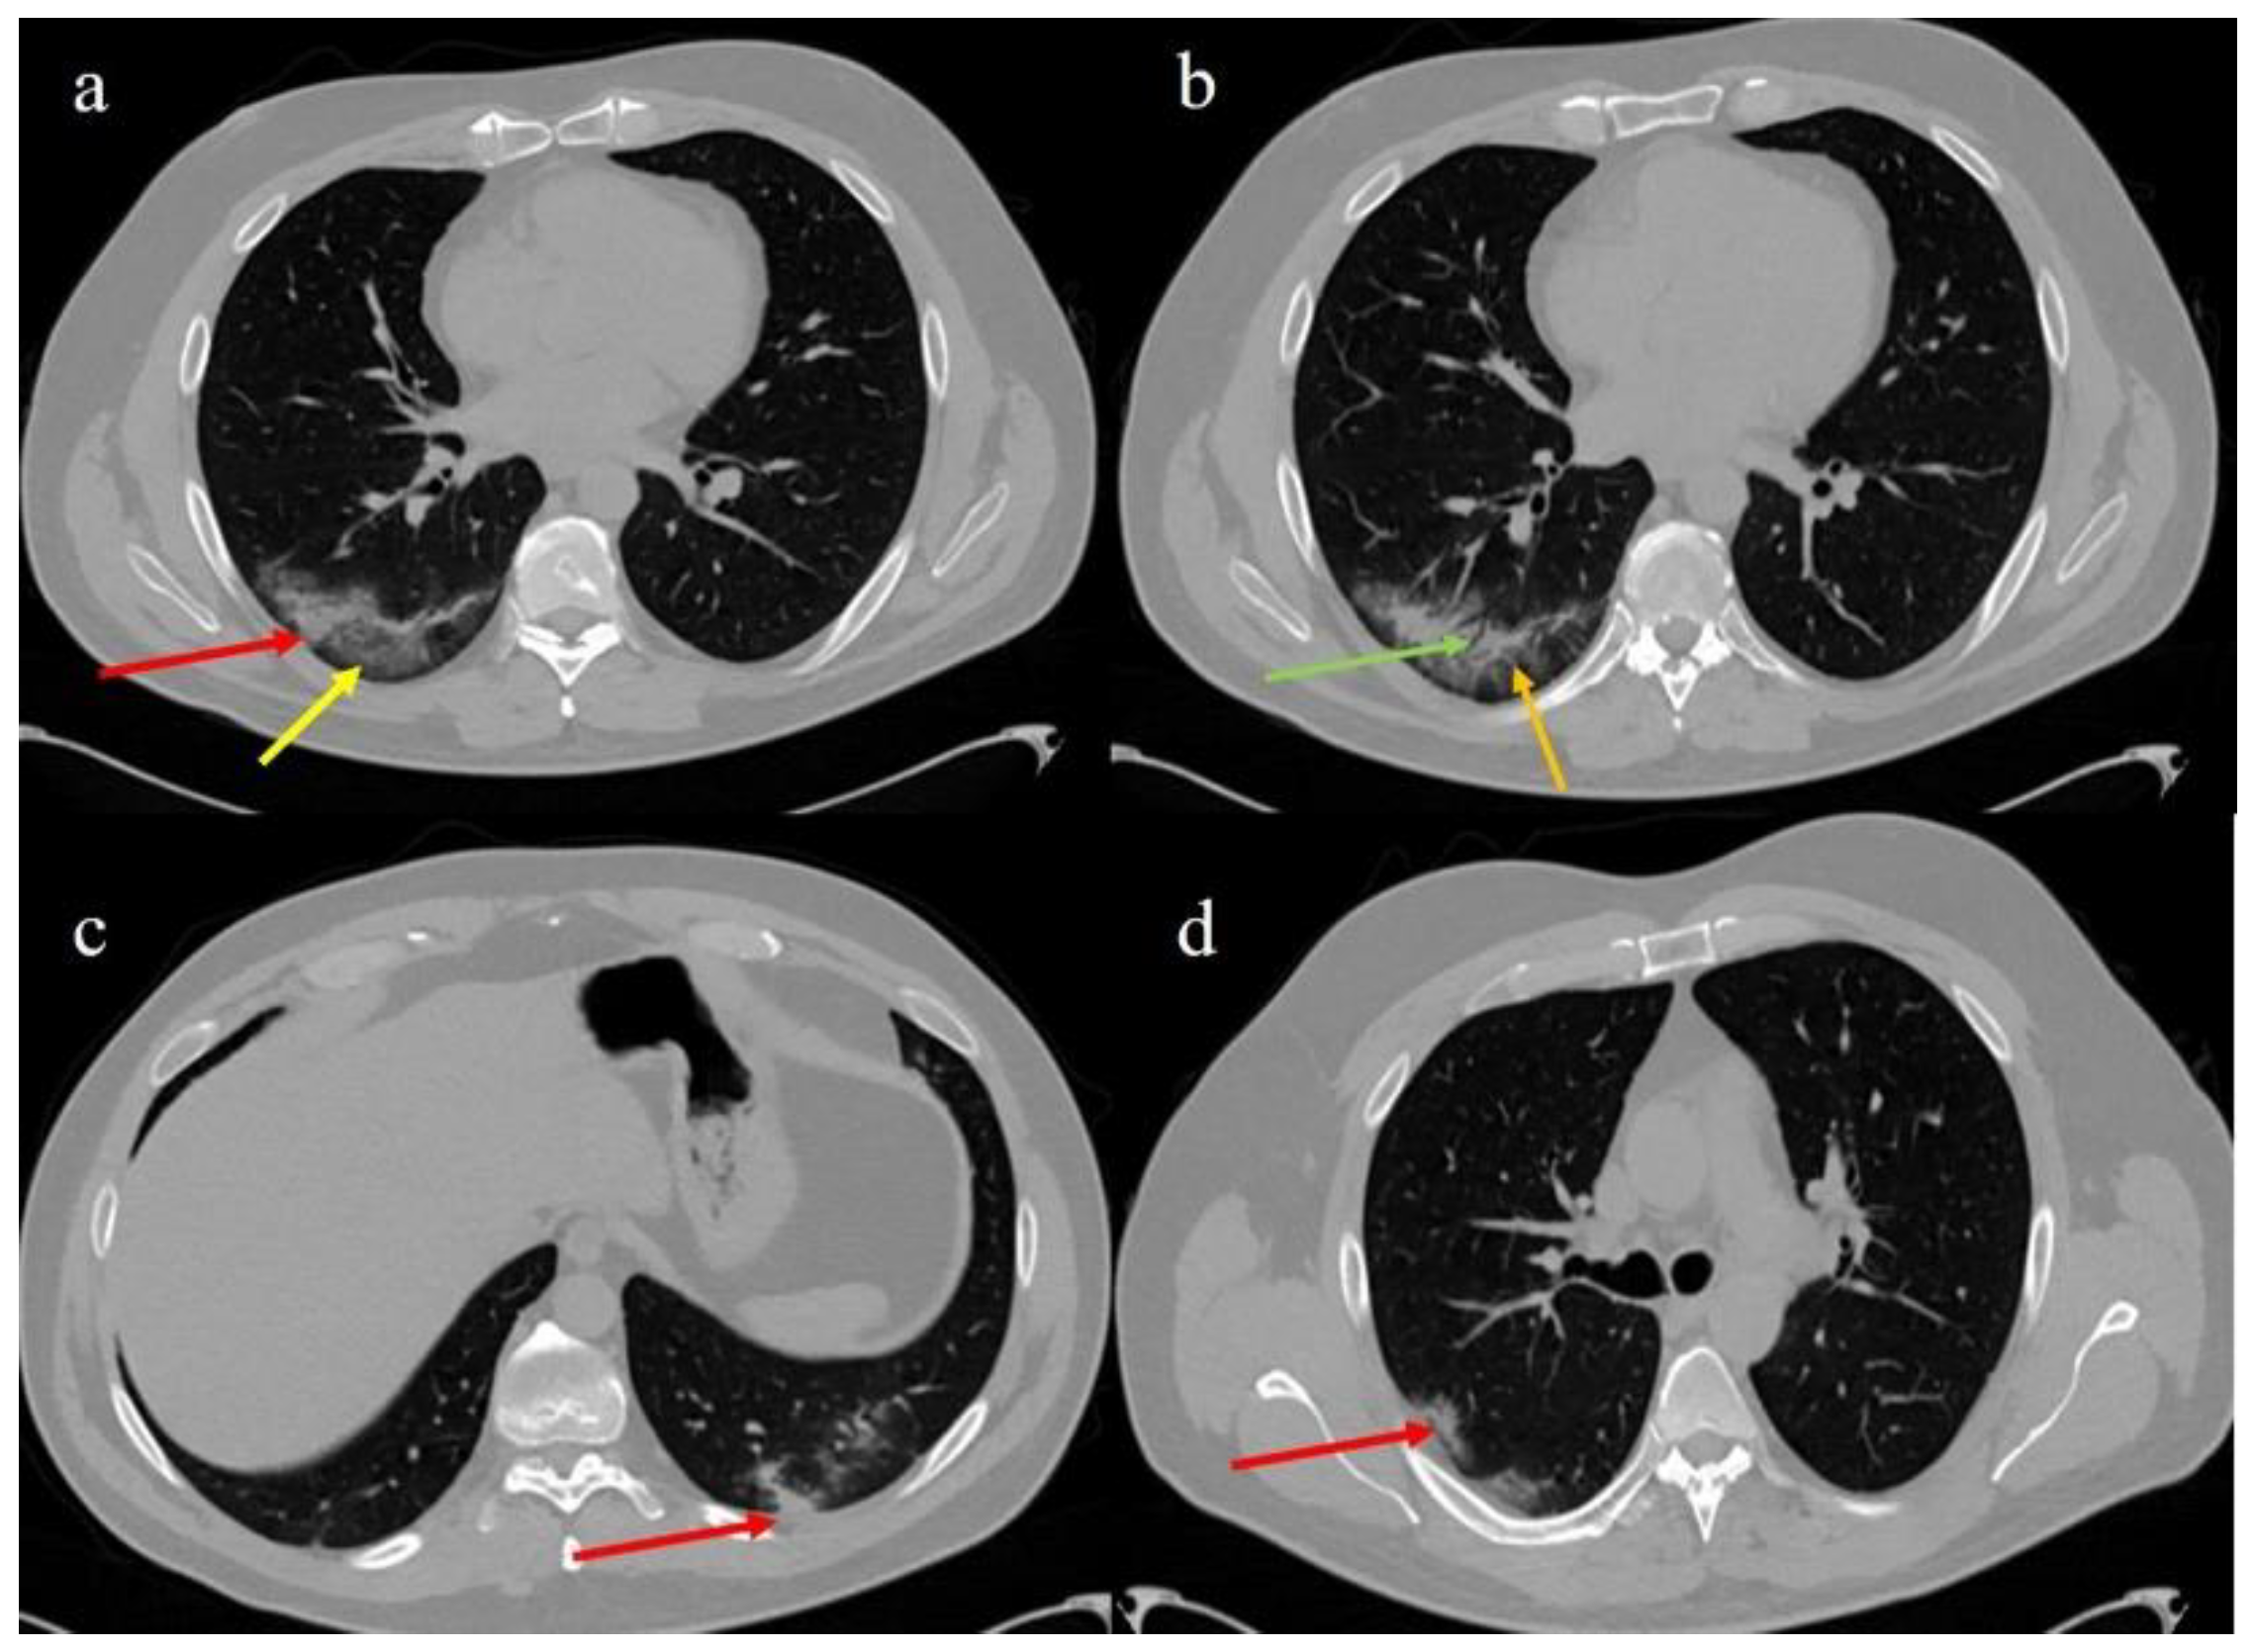

- Brogna, B.; Bignardi, E.; Brogna, C.; Alberigo, M.; Grappone, M.; Musto, L.; Megliola, A.; Salvatore, P.; Fontanella, G. Typical CT findings of COVID-19 pneumonia in patients presenting with repetitive negative RT-PCR. Radiography 2020. [Google Scholar] [CrossRef]